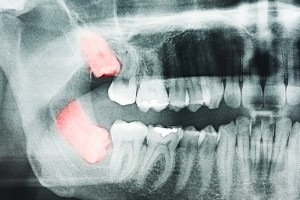

One of the many problems that can develop with wisdom teeth is an abscess. This painful condition occurs when pus, the product of an infection, collects in tooth’s inner core, which is known as the pulp. An abscess can also develop between a tooth’s root and the gum tissue. In the case of an impacted tooth, an abscess may even crop up between the tooth and the flap of gum tissue that partially covers it.

Any tooth can develop an abscess, but the wisdom teeth are particularly susceptible because they tend to collect the bacteria that lead to abscesses, as it’s hard to keep wisdom teeth clean. This is especially when the wisdom teeth are only partially erupted, which happens in so many patients because the jaws of modern-day humans are not wide enough for the wisdom teeth to fit.